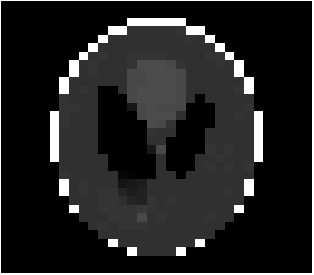

When the total variation of an image is minimized, noise is removed and texture is smoothed out while the edges and important details are maintained. In the context of compressed sensing, the discrete gradient can be used as a sparsifying basis. It was proven by Needell and Ward [16] that even with undersampling, total variation minimization can recover an image robustly. Indeed, many natural images do not vary much in intensity from pixel to pixel which makes them compressible with respect to their discrete gradients. For example, the Shepp-Logan Phantom image is sparser with respect to its discrete gradient than its wavelet representation, see Figure 7.

Due to its wide use in image processing, we consider the use of gradient sparsification with LACS-MRI. We show below that it is possible to produce image reconstructions with significantly higher Reconstruction SNR using gradient sparsification. We have repeated some of the simulations from above for different compression levels, , using the gradient transform to sparsify instead of the wavelet transform. We will refer to this as ”LACS-MRI with gradient sparsity.” We compared the performance of each sparsification method at each compression level using LACS-MRI and then compared this to the L1-W method. Again, we use a reference image and a follow-up image that we hope to recover as in Figure 8. We consider here only the phantom image, as it serves as a prime candidate for gradient sparsification, and is small enough that evaluation of all PDFs is computationally feasible.

We re-ran simulations for cases 7, 8, 17, and 18 on the phantom. Over 30 trials, using the gradient on the phantom image resulted in much higher RSNR for every single case. Cases 7 and 17 both also outperformed cases 8 and 18 every time by about 13%. These cases both used the variable density sampling method and LACS-MRI. Figure 9 shows the reconstruction from Case 17. The recovered image using LACS-MRI with wavelet sparsity is more pixelated near the tumor while LACS-MRI with gradient sparsity produced an almost perfect reconstruction. Figure 11 shows the great disparity between the two sparsifying methods. On average, the four phantom reconstructions using the gradient only needed to sample about 6% of the data to achieve the same RSNR that the reconstructions using the wavelets did at 21% sampling.